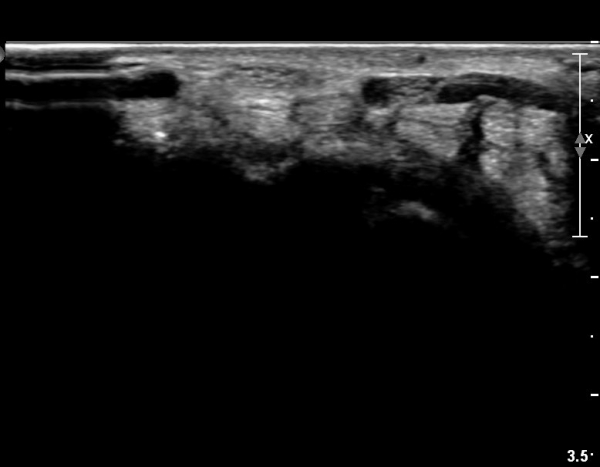

Á¤Á߽Űæ Á¾´Ü¸é°Ë»ç¿¡¼­µµ ¼Õ¸ñ ¸»´ÜºÎ¿¡¼­ ¼ö±Ù°ü ±ÙÀ§ºÎ±îÁö À̾îÁø Àú¿¡ÄÚ

Á¾¾çÀÌ °üÂûµÊ(»çÁø 8, 9, 10, 11).